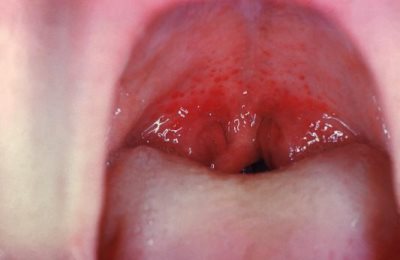

Условно симптомы фарингита можно разделить на характерные для всех форм заболевания и специфические. Характерными практически для любого фарингита будут боль при глотании, ощущение инородного тела в горле, першение.

Фарингоскопия определяет покраснение стенок глотки, а также нёбных дужек. Для вирусной этиологии заболевания будут характерны симптомы обще интоксикации, а также проявления поражения других органов – к примеру, пищеварительной системы.